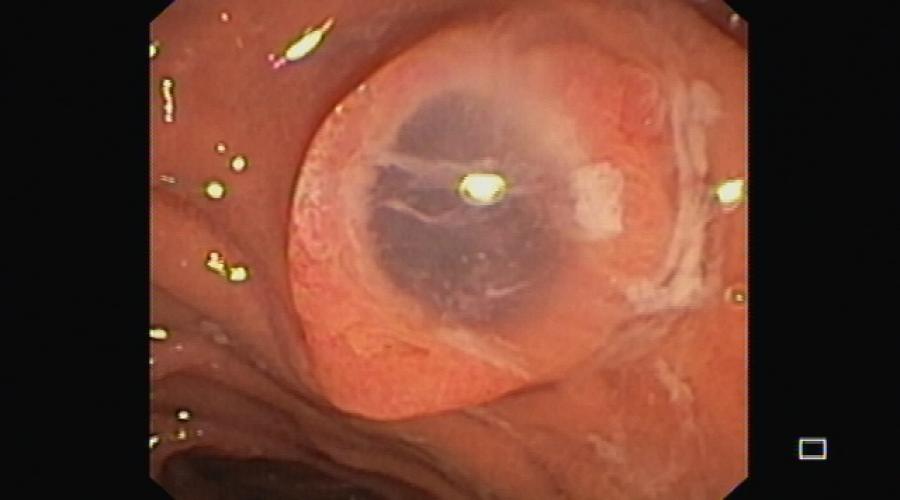

Obstrução do trato de saída gástrico

Observe em um minuto o algoritmo de atuação proposto.Aprofunde conhecimento ou reveja mais globalmente este tema nos artigos...